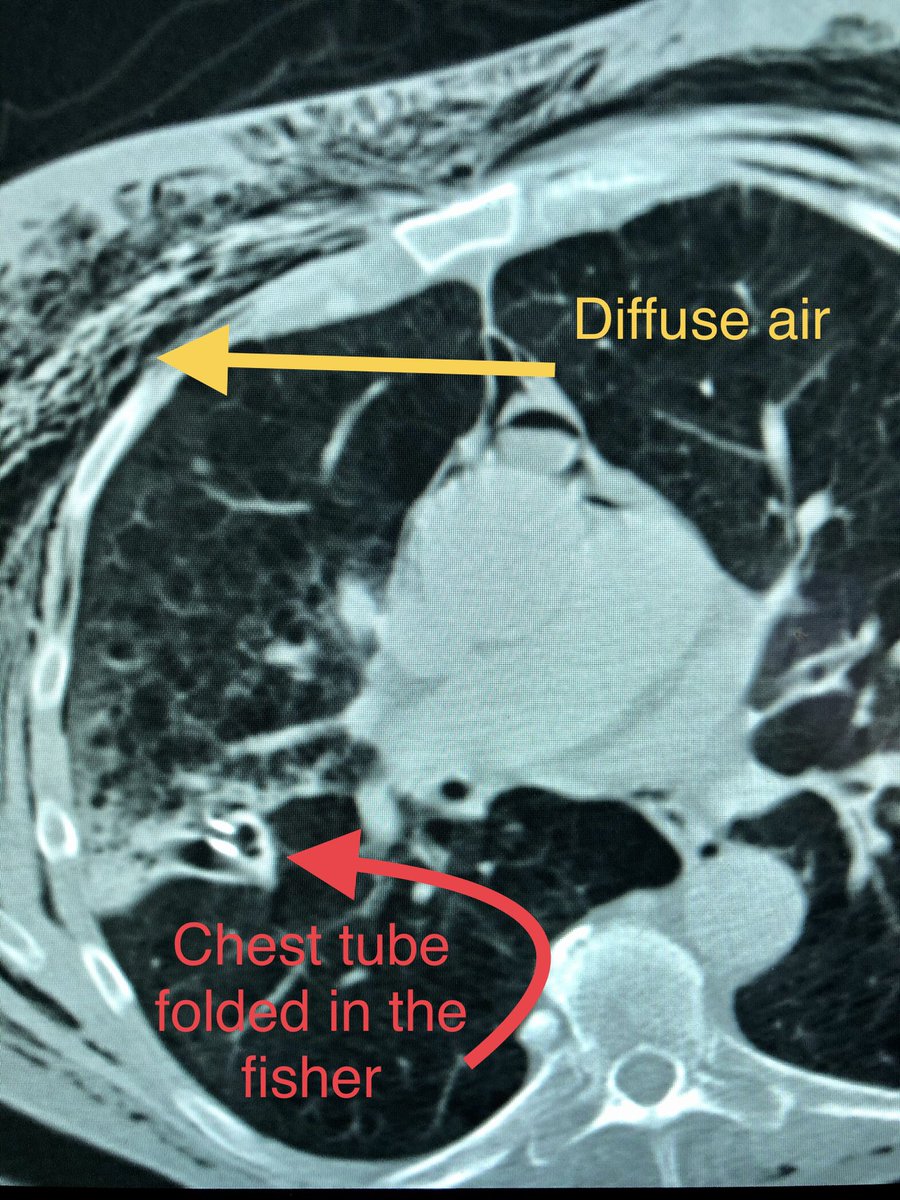

@masi_zachary @SIR_ECS @bachakzaimd @sarelgaurmd @joeirad Classic fissural chest tube. Love these cases. Fluoro guidance? How do you like APDL vs dawson mueller for your PTX chest tubes? And how do you decide your sizing? I usually do anterior approach 8.5 Fr dawson mueller